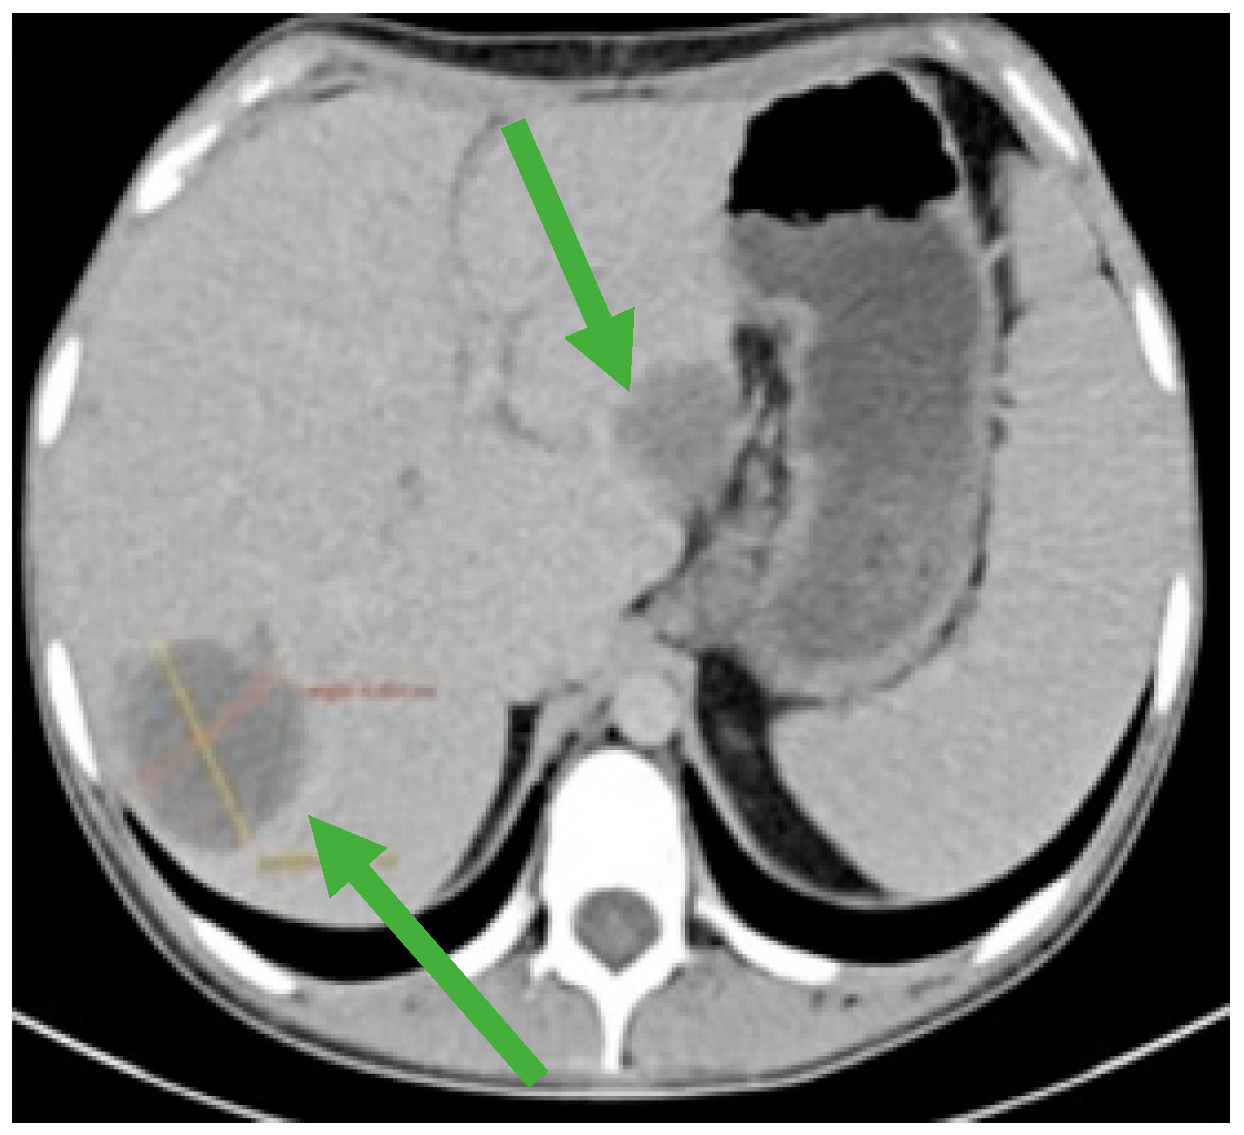

Figure 3.

Hepatomegaly and multiple liver metastases (green arrows).

During the maintenance therapy with oral etoposide, the plasma beta HCG was highly increased (6228 mIU/mL), so we decided to start third line chemotherapy with GOP (gemcitabine 800 mg/sqm day 1 and 8, paclitaxel 80 mg/sqm day 1 and 8, oxaliplatin 130 mg day 1, q3w). After five cycles, we observed a new biological and imagistic progression (Figure 3 and Figure 4) in the size and number of the liver and lung metastases that appeared.